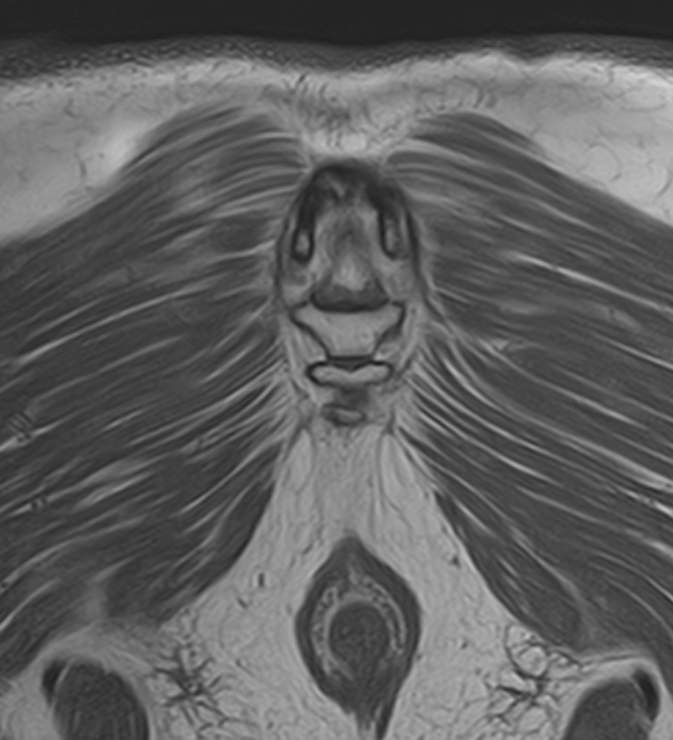

Боль в нижней части спины является наиболее распространенным симптомом различных заболеваний позвоночника, которые поражают пояснично-крестцовый отдел. В ряде случаев боли в нижних отделах спины сочетаются с кокцигодинией, то есть болями в рудиментарной части позвоночного столба – копчике. Причинами появления таких симптомов могут быть воспалительные процессы, дегенеративно-дистрофические заболевания позвоночника, опухолевые поражения данной анатомической области.

МРТ является наиболее информативным способом диагностики заболеваний позвоночника, так как позволяет оценить состояние костных структур позвонков, расположенную здесь часть спинного мозга с нервными корешками, а также связки, сухожилия и окружающие мягкие ткани. Магнитно-резонансная томография превосходит все другие методы диагностики не только по информативности, но и по безопасности, так как в основе метода лежит использование внешнего магнитного поля и отсутствует вредное для организма воздействие облучения, свойственное рентгену.

Для выявления причин появления кокцигодинии и болей в нижней части спины в клинике «Доступная медицина» проводится комплексное обследование МРТ пояснично-крестцового отдела + копчик, включающее два протокола исследования каждой анатомической области.